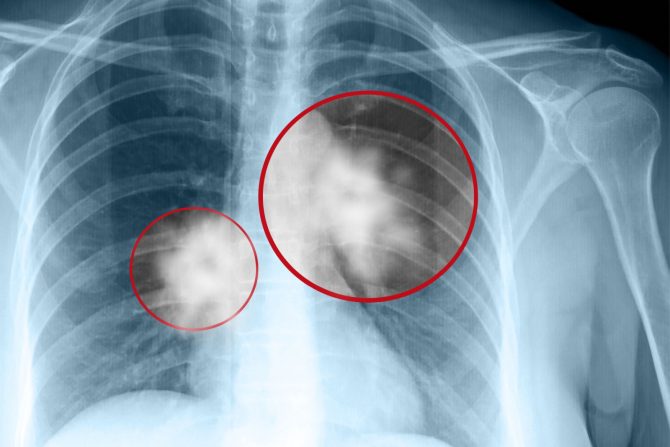

Osobe koje su dobile karcinom pluća, a nikada ranije nisu pušile obično imaju veću učestalost mutacija koje imaju veze sa razvojem raka pluća

Rak pluća, koji se uglavnom dovodi u vezu sa muškarcima i osobama koje puše, sada se češće dijagnostikuje kod žena mlađih i srednjih godina, pokazuju rezultati novog istraživanja. Studija, objavljena prošle nedelje u JAMA Oncology, otkrila je da su stope novodijagnostikovanih slučajeva raka pluća bile veće kod žena starosti od 35 do 54 godine nego kod muškaraca istog uzrasta – uprkos opštem trendu pada stope incidencije raka pluća.